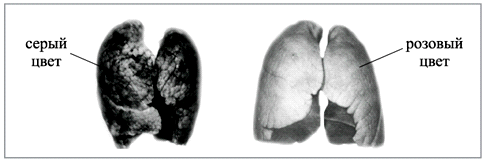

Продукты пиролиза и горения при затягивании попадают в дыхательные пути, легкие, желудочно-кишечный тракт, образовавшиеся твердые частицы и смолы оседают на поверхности (стенках) дыхательных путей, альвеолах (легочных мешочках), т.е. легкие засоряются (рис. 10). Организм на это реагирует кашлем, воспалением, аллергией, перерождением клеточной ткани (т.к. многие вещества табачного дыма обладают канцерогенным действием), эмфиземой легких (необратимая дегенерация легочной ткани).

Рис. 10. Легкие курильщика (слева) и некурящего человека